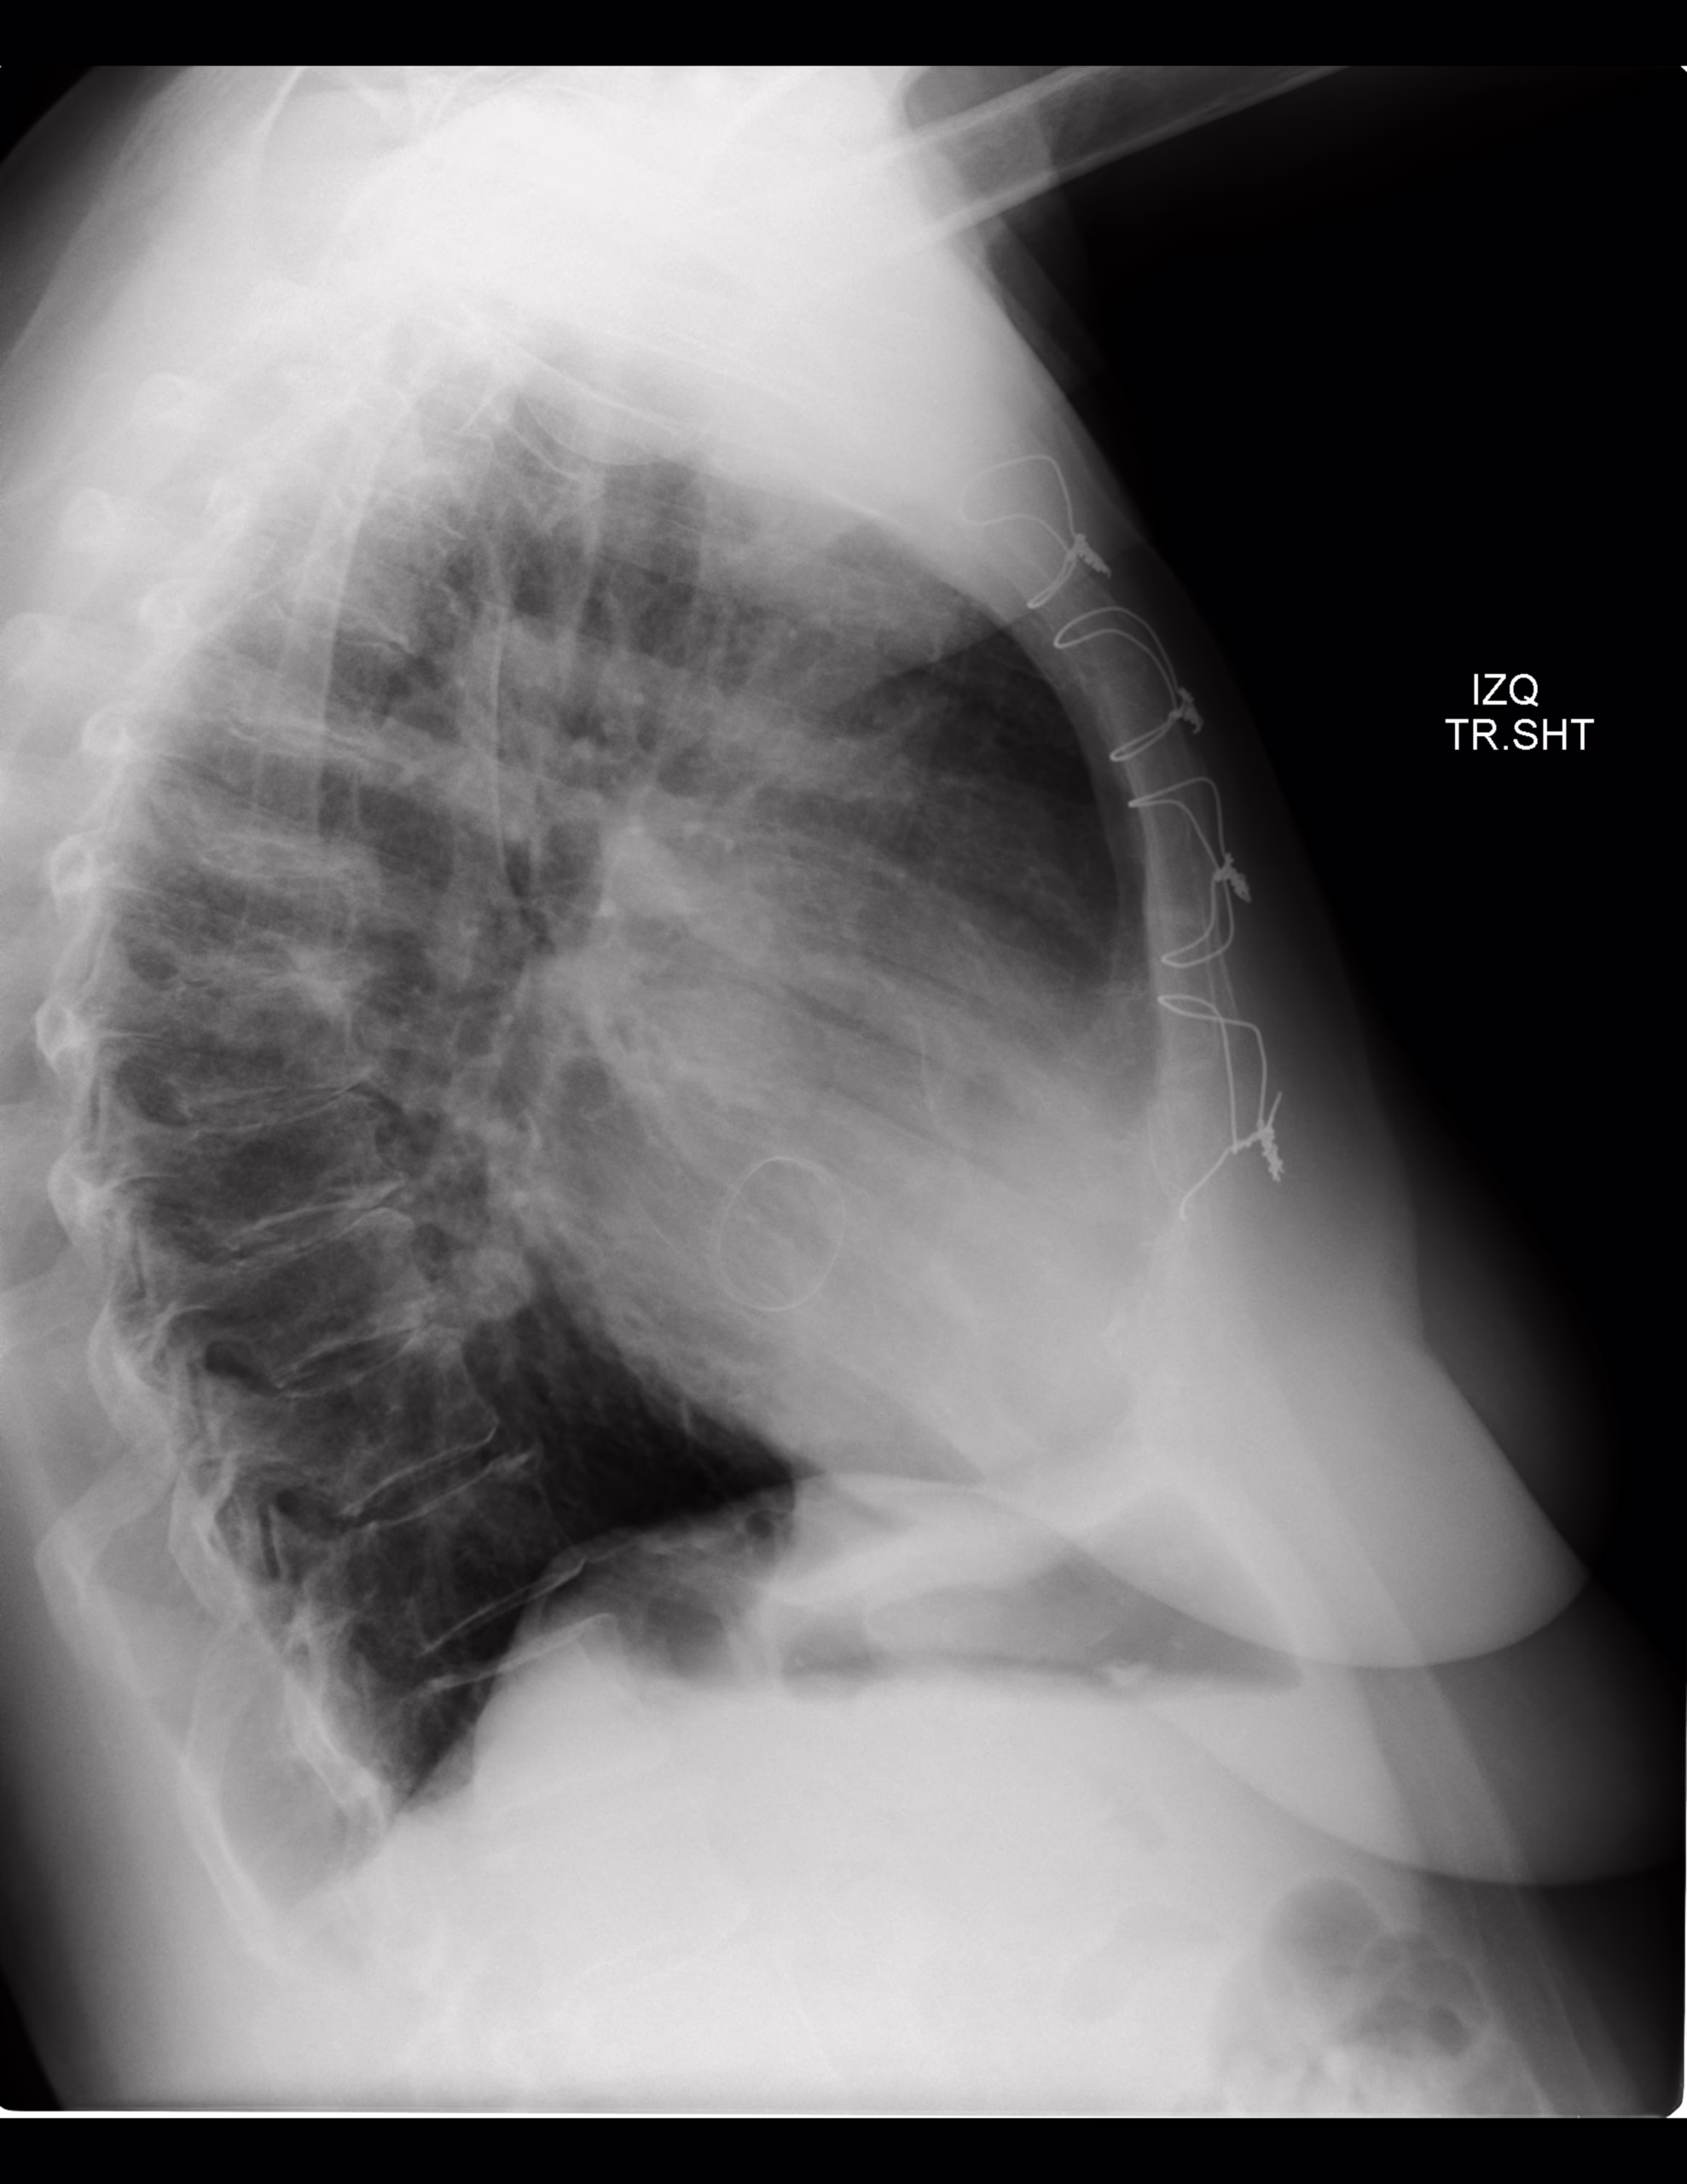

PA Y LATERAL DE TORAX

-Corazón, central, con índice cardiotorácico de 0.57. Existe material radiopaco en topografía de válvula mitral.

-Espacio retroesternal con leve disminución de su amplitud.

IMAGEN DE REMPLAZÓ DE VÁLVULA MITRAL.

EXISTE ESTERNOTOMÍA MEDIA, CON MATERIAL METÁLICO.

Remplazo valvular mitral